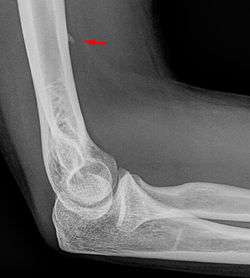

![]() Small supracondylar process seen on a lateral radiograph of the elbow | |

The supracondylar process of the humerus is a bony projection on the anteromedial aspect of the upper arm bone (humerus), about 5 cm above the medial epicondyle. It is directed downward, forward and medially pointing to the medial epicondyle. It is an anatomical variation which occurs in about one percent of all people. A fibrous band, Struthers ligament, may connect this process to the medial epicondyle.

Supracondylar processes are usually asymptomatic, but may be palpable as a mass on the upper arm. They are most commonly found as an incidental finding on radiographs made for other reasons, but occasionally isolated fractures of the process itself may lead to its discovery. Rarely, presence of the process and a connecting ligament may lead to compression of the brachial artery and the median nerve, leading to pain, paresthesia and/or ischemia.